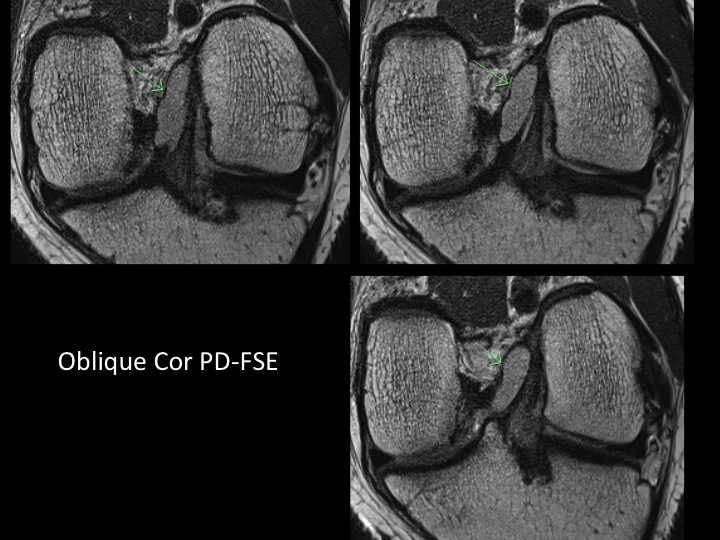

There is a chronic tear of the anteromedial bundle of the ACL with an intrasubstance ganglion. In the Obl Cor PD images it appears that there is complete or nearly complete tear of the anteromedial bundle, which is difficult to quantify in the Sag or axial plane. With this case being the exception, I rarely find that these Obl Cor images help much. What is the consensus? Do you use Obl Cor? Did you and have you abandoned it? Is it really worth the additional imaging time? Reference article.

anteromedial bundle of anterior cruciate ligament ( RID2782 )